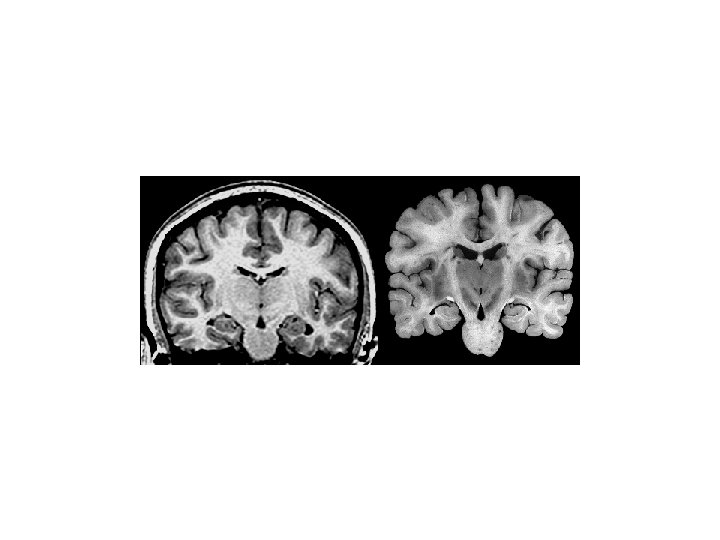

Sulcus Gyrus